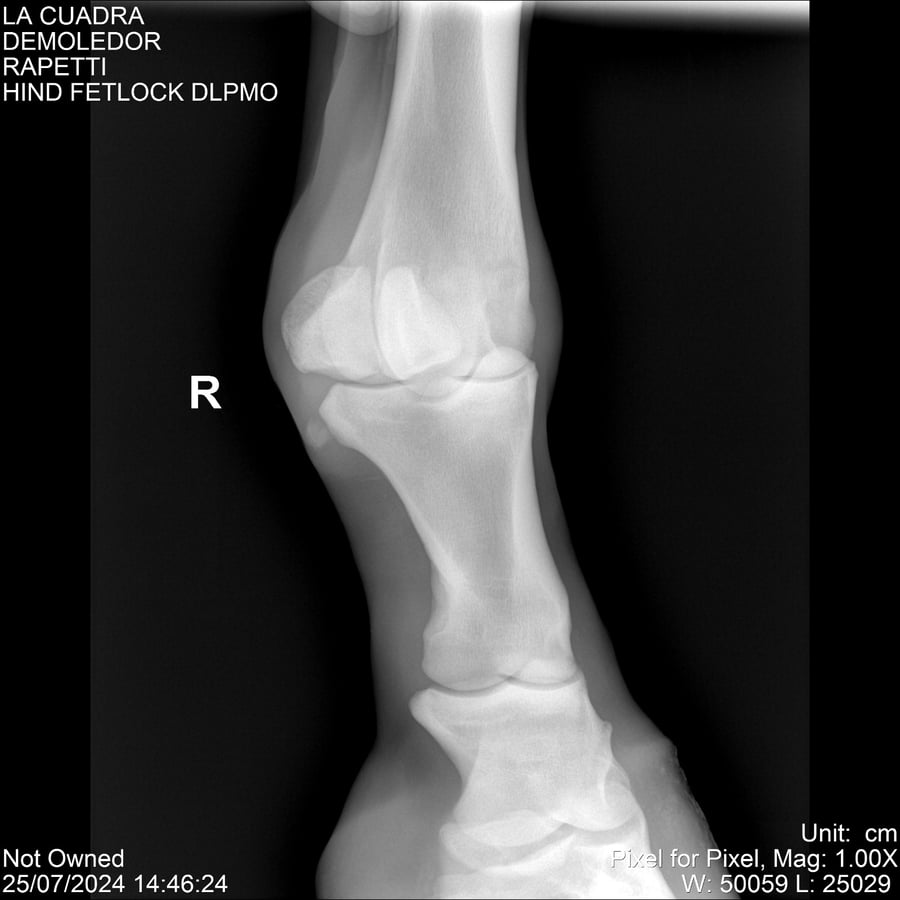

LOTE 14, DEMOLEDOR 🔥 🔥 🔥 Lote Anterior Volver al remate Lote Siguiente Ficha Contacto Montevideo - Ficha del Lote Identificador: #284454 Categoría: Yeguarizos Montevideo - 89 Visualizaciones ClicData Contacto Empresa: Abelenda N. R., Walter Hugo Nombre*: Teléfono* : E-mail* : Mensaje Enviar Registrese gratis Este contenido Exclusivo está disponible sólo para usuarios registrados Ingresar